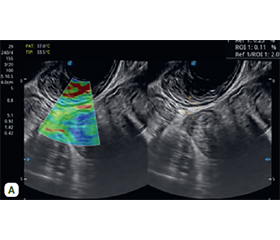

Актуальність. Колоноскопія з біопсією залишається золотим стандартом діагностики запальних захворювань кишечника (ЗЗК). Однак цей метод має низку обмежень, особливо у важких клінічних умовах, тому зростає потреба в менш інвазивних методах візуалізації. Одним із таких методів є трансректальне ультразвукове дослідження (ТРУЗД), яке забезпечує візуалізацію стінки прямої та дистального відділу сигмовидної кишки з високим рівнем деталізації. ТРУЗД дозволяє кількісно оцінити товщину кишкової стінки, стратифікувати її шари, виявити гіперваскуляризацію, характерну для активного запалення, а також інфільтративні й фіброзні зміни. За даними сучасних клінічних досліджень продемонстровано високу чутливість і специфічність цього методу, що робить доцільним більш широке його використання в клінічній практиці. Однак, незважаючи на численні переваги, ТРУЗД у клінічній практиці застосовують недостатньо, хоча воно є перспективним неінвазивним інструментом діагностики й моніторингу пацієнтів із ЗЗК. Мета: проаналізувати можливості й клінічну ефективність трансректального ультразвукового дослідження в діагностиці виразкового коліту (ВК) і хвороби Крона (ХК). Матеріали та методи. ТРУЗД проводили на ультразвуковому сканері експертного класу SonoScape S60 з використанням низькочастотного конвексного датчика 3,5 МГц та ректовагінального конвексного датчика 6 МГц. Використовували трансперинеальний і трансректальний доступи. Результати. Потовщення стінки прямої кишки > 5 мм мали 100 % хворих. Товщина стінки прямої кишки в пацієнтів із ХК була вірогідно нижчою, ніж в осіб із ВК: (5,99 ± 0,42) мм проти (7,12 ± 0,20) мм (р = 0,01). Товщина слизового шару при ВК перевищувала цей показник при ХК в 1,8 раза (p = 0,05), а товщина підслизового шару — в 1,3 (p = 0,01). Товщина м᾽язового шару в пацієнтів із ХК, навпаки, була вірогідно вищою, ніж в осіб із ВК: (1,69 ± 0,21) мм проти (1,17 ± 0,04) мм (p = 0,05). Товщина стінки прямої кишки ((6,80 ± 0,21) мм та (8,15 ± 0,42) мм, р = 0,04) і товщина підслизового шару ((4,14 ± 0,21) мм проти (5,28 ± 0,28) мм, р = 0,008) вірогідно відрізнялися при середньому й тяжкому ступені ВК. Майже у 86,7 % обстежених пацієнтів із тяжким ВК спостерігався 3 ступінь щільності кровотоку у стінці прямої кишки, тоді як при ХК середньої тяжкості 61,5 % пацієнтів мали 1 ступінь. При проведенні еластометрії стінки прямої кишки відмічалася тенденція до збільшення коефіцієнту деформації в пацієнтів із ХК порівняно з особами з ВК. ROC-аналіз дозволив установити високу значущість товщини м’язового шару в диференціальній діагностиці ВК та ХК. Висока діагностична цінність була також отримана щодо товщини підслизового шару при оцінці ступеня тяжкості ВК. Висновки. ТРУЗД є ефективним неінвазивним методом оцінки запальних захворювань кишечника. Допплерівське сканування дозволяє оцінити ступінь васкуляризації стінки прямої кишки, що корелює з клінічною активністю ЗЗК. Еластометрія стінки прямої кишки корисна у визначенні тяжкості запалення. Товщина стінки прямої кишки та підслизового шару має високу прогностичну цінність у виявленні тяжкого ВК. Товщина м’язового шару > 1,3 мм може бути використана як допоміжний критерій у диференціальній діагностиці ВК та ХК.

Background. Colonoscopy with biopsy remains the gold standard for the diagnosis of inflammatory bowel disease (IBD). However, this method has a number of limitations, especially in severe clinical conditions. In this regard, there is a growing need for less invasive imaging methods. One of these methods is transrectal ultrasound (TRUSD), which provides high-resolution imaging of the wall of the rectum and distal sigmoid colon. TRUSD allows for quantitative assessment of the intestinal wall thickness, stratification of its layers, detection of hypervascularisation characteristic of active inflammation, as well as identification of infiltrative and fibrotic changes. The data of modern clinical trials demonstrate the high sensitivity and specificity of this method, which makes it advisable to use TRUSD more widely in clinical practice. Despite its numerous advantages, TRUSD remains an underutilised method in clinical practice, although it is a promising non-invasive tool for the diagnosis and monitoring of patients with IBD. The aim of the study was to analyse the possibilities and clinical effectiveness of transrectal ultrasound in the diagnosis of ulcerative colitis (UC) and Crohn’s disease (CD). Materials and methods. TRUSD was performed on an expert-class ultrasound scanner SonoScape S60 using a 3.5 MHz low-frequency convection transducer and a 6 MHz recto-vaginal convection transducer. Transperineal and transrectal approaches were used. Results. Thickening of the rectal wall > 5 mm was typical for 100 % of patients. The wall thickness was significantly lower in patients with CD compared to those with UC — (5.99 ± 0.42) mm vs. (7.12 ± 0.20) mm, respectively (p = 0.01). The thickness of the mucosal layer in UC was 1.8 times higher than in CD (p = 0.05), and the thickness of the submucosal layer was 1.3 times higher (p = 0.01). On the contrary, the thickness of the muscular layer in patients with CD was significantly higher than in those with UC — (1.69 ± 0.21) mm vs. (1.17 ± 0.04) mm (p = 0.05). The wall thickness ((6.80 ± 0.21) mm vs. (8.15 ± 0.42) mm, p = 0.04) and submucosal layer thickness ((4.14 ± 0.21) mm vs. (5.28 ± 0.28) mm, p = 0.008) significantly differed between moderate and severe UC. Almost 86.7 % of the examined patients with severe UC had grade 3 blood flow density in the rectal wall, whereas in moderate UC, 61.5 % of patients had grade 1. When performing elastometry of the intestinal wall, there was a tendency to increase the strain coefficient in patients with CD compared to UC. The ROC analysis allowed us to establish the high quality of the diagnostic indicator — the thickness of the muscular layer — for the differential diagnosis of UC and CD. High diagnostic value was also obtained for the thickness of the submucosal layer in assessing the severity of UC. Conclusions. TRUSD is an effective non-invasive method for evaluating inflammatory bowel diseases. Doppler scanning allows to assess the degree of vascularisation of the intestinal wall, which correlates with the clinical activity of IBD. Intestinal wall elastometry is useful in determining the severity of inflammation. The thickness of the intestinal wall and submucosa have a high prognostic value in detecting severe UC. A muscular layer thickness of 1.3 mm can be used as an auxiliary criterion for the differential diagnosis between UC and CD.